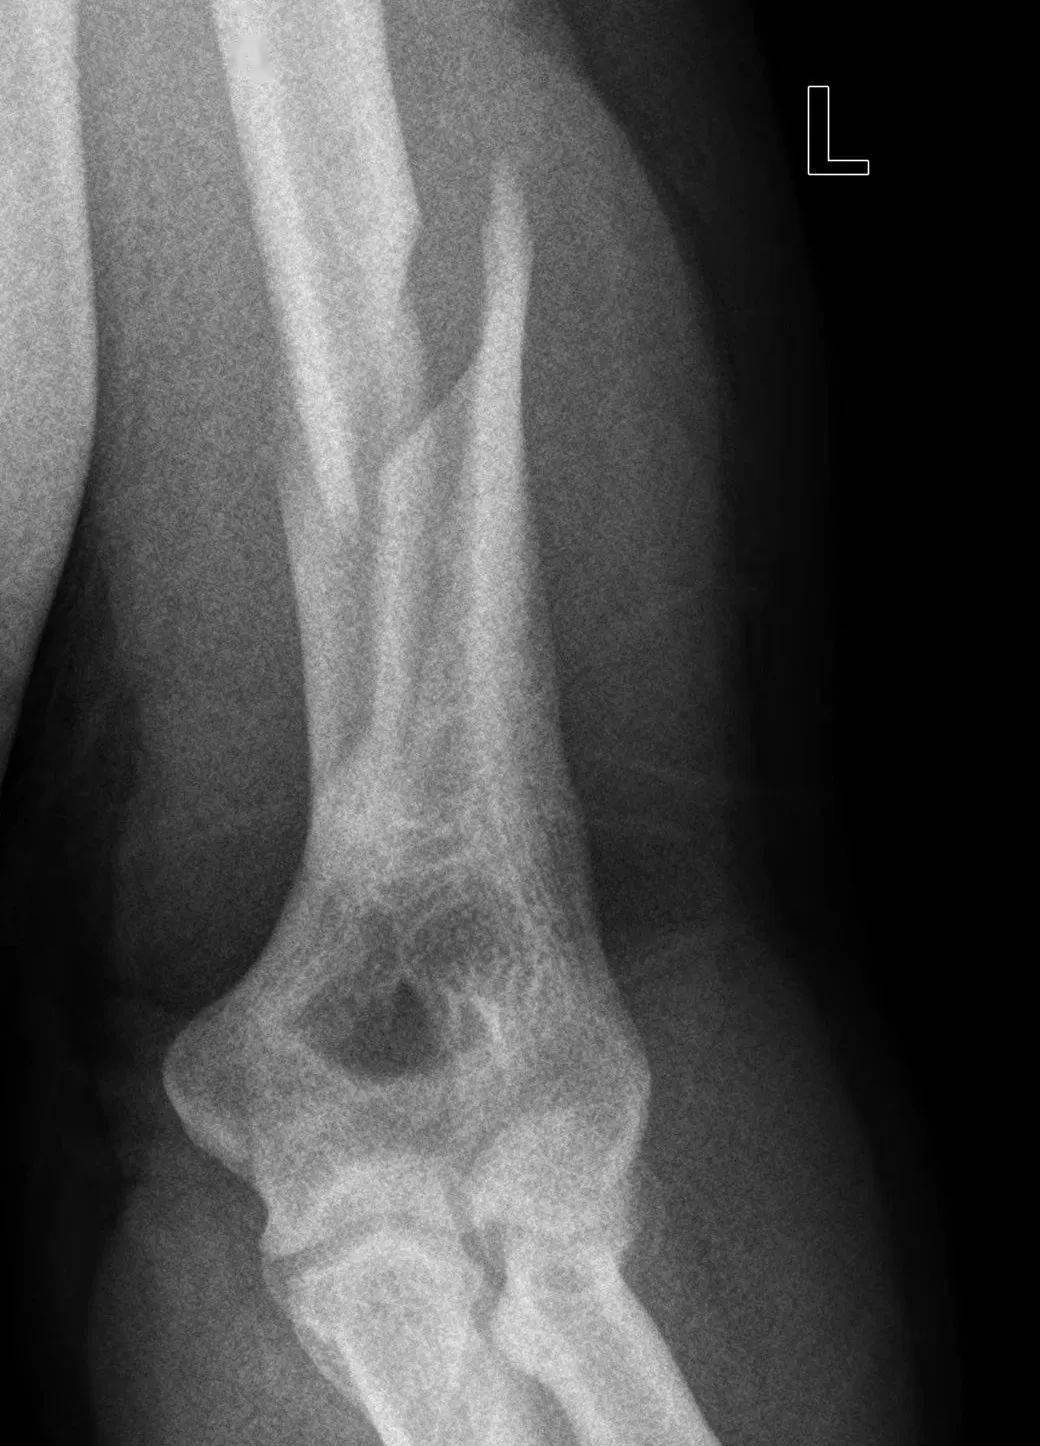

由于存在共同的受伤机制,扳手腕导致的肱骨干骨折表现极为相似。这类骨折几乎都是肱骨远端三分之一螺旋形骨折,半数伴有蝶形骨折片,在AO/OTA分型中分别为12-A1型和12-B1型,可伴有桡神经损伤。

图 扳手腕导致的肱骨干骨折